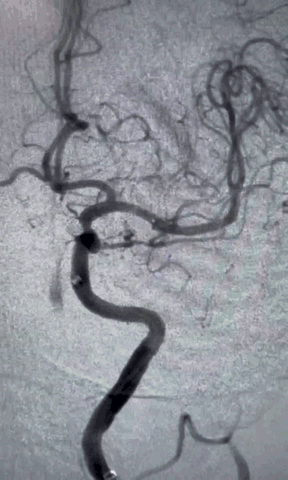

右侧股动脉穿刺,置8F鞘管,泥鳅导丝携6F 90cm Locaste输送导管内衬125cm多功能单弯导管超选至左侧颈内动脉C1段,6F 115cm Skathi远端通路导管到达C4段。

依据动脉瘤3D,调整机架位置使得动脉瘤及载瘤动脉显影最佳,Echelon-10微导管塑形理想,顺利超选至瘤内,先尝试单纯弹簧圈栓塞,必要时再采用支架辅助。

按大小顺序依次填塞弹簧圈(Jasper SS 3*8 Axium Prine 2*4、1*3)且弹簧圈成篮稳定,最终达到致密栓塞效果,手术过程顺利。